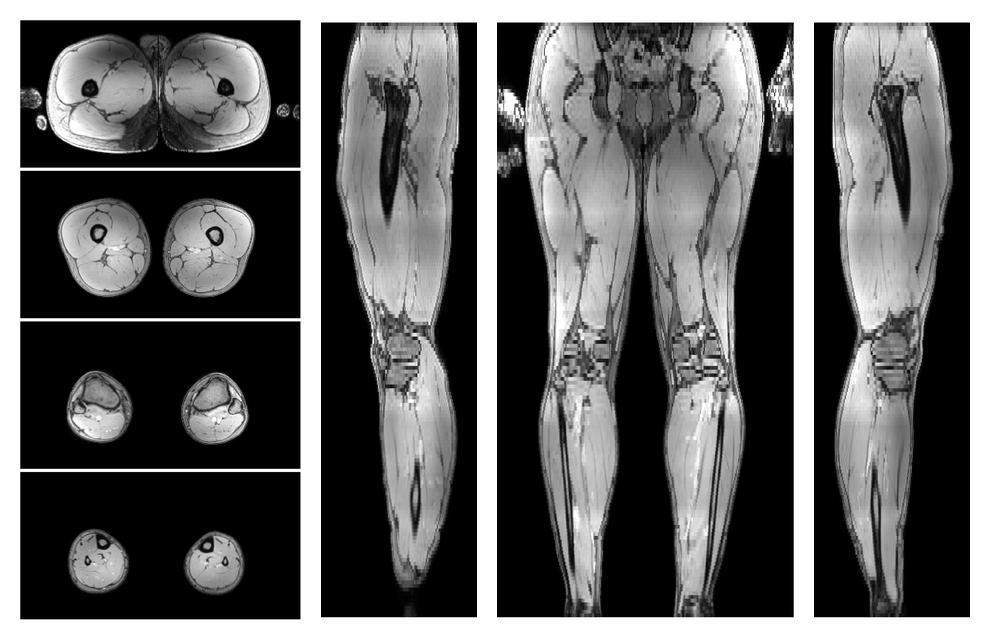

• Out phase image

The out-phase image of the dixon reconstruction for water fat quantification.